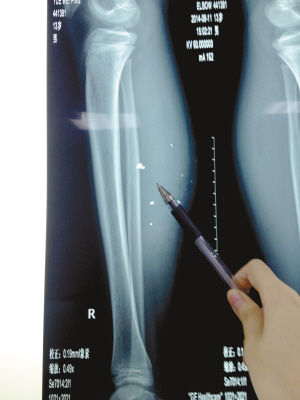

X光片顯示:手機電池內(nèi)的物質(zhì)被炸進了小平的右小腿里

8月10日凌晨,小平轉(zhuǎn)院至重慶醫(yī)科大學附屬兒童醫(yī)院。小平的主治醫(yī)生骨科二病房周悅航醫(yī)生介紹,入院時小平右小腿腫脹,經(jīng)檢查,發(fā)現(xiàn)有爆炸傷伴異物殘留。傷口較深,約1.5厘米~2厘米,手機爆炸后進入患兒小腿的異物約有10處。周悅航說,由于進入皮膚的異物較多,已深入肌肉,且比較分散,最深的一塊貼近骨頭,可能需要多次手術。

另外,醫(yī)生擔心手機爆炸后金屬物進入患兒體內(nèi)可能會對患兒肌肉造成損傷,所以需盡快手術。據(jù)悉,8月14日上午,小平將接受小腿爆炸傷清創(chuàng)與異物取出術。